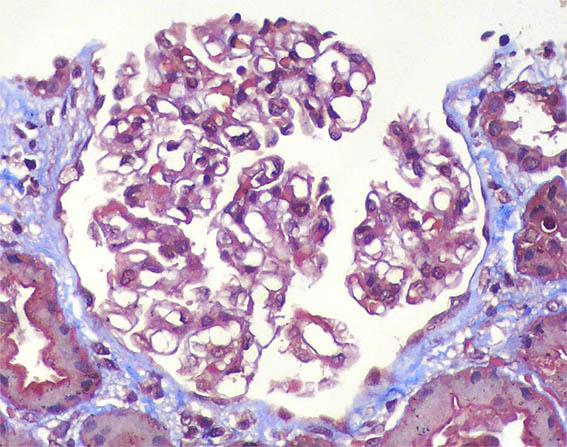

Figura 9. Tricrómico de Masson, X400.

Figura 10. Plata-metenamina, X400.